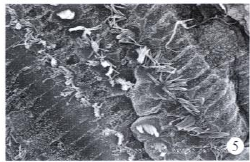

该项目通过动物模型的建立、血铅和电生理检测、形态学观察、新生儿听力联合聋病易感基因的联合筛查技术、易感基因突变分子病因学的研究等方法明确儿童先天性耳聋的发病机理,并进行聋病患儿的听力补偿与干预、儿童听力障碍的言语康复等手段防治。通过17年的研究取得了以下成果:(1)明确环境和药物引发感音神经性耳聋的发病机理,探索相应的保护机制;(2)阐明了新生儿早期听力联合聋病基因筛查的价值,首次揭示了我省聋儿易感基因总的突变率及突变形式,绘制了我省耳聋基因突变图谱。首次发现了Waardenburg综合征SOXl0基因新发突变位点;(3)规范了儿童听力障碍的治疗,显著提高听力补偿后的言语康复效果;(4) 通过标准化防治体系的建立,建成具有省内重要影响的昆明市儿童听力障碍疾病诊治创新团队和工程技术中心,成为云南省和昆明市的重点学科。

电镜下高铅暴露组2周后毛细胞出现倒伏、排列紊乱(×400) | The de novo mutation in SOX10 gene [NM_006941.3 c.163A>T] | 微创人工耳蜗植入 |